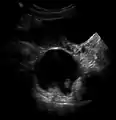

Dermoid cyst in vaginal ultrasonography

A complex cyst due to a dermoid as seen on ultrasound